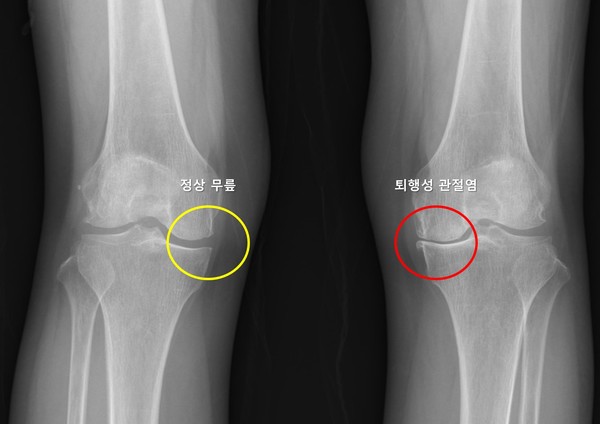

무릎 퇴행성 관절염은 연골의 점진적인 손상과 관절 구조물의 퇴행성 변화로 인해 발생하는 질환으로, 통증과 운동 제한을 유발하며 삶의 질을 크게 저하시킬 수 있다.

전 세계 인구의 약 16~30%에서 발생하며, 고령화 사회로 접어들면서 그 유병률은 꾸준히 증가하는 추세다. 많은 환자들이 한쪽 무릎에 관절염이 생긴 뒤 수년 내 반대쪽 무릎에서도 통증이나 구조적 변화가 나타나는 경험을 하지만, 이러한 양측성 진행이 모든 환자에게서 동일하게 나타나는 것은 아니며, 이를 예측하려는 연구는 부족한 상황이었다.